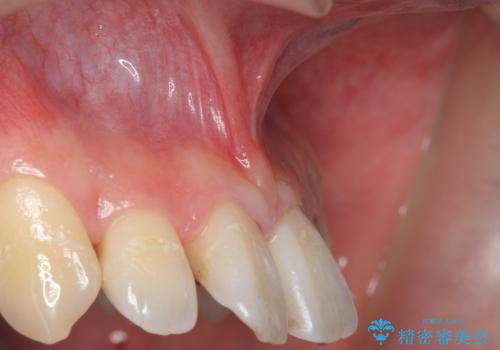

上唇小帯切除

担当医 青山卓弘